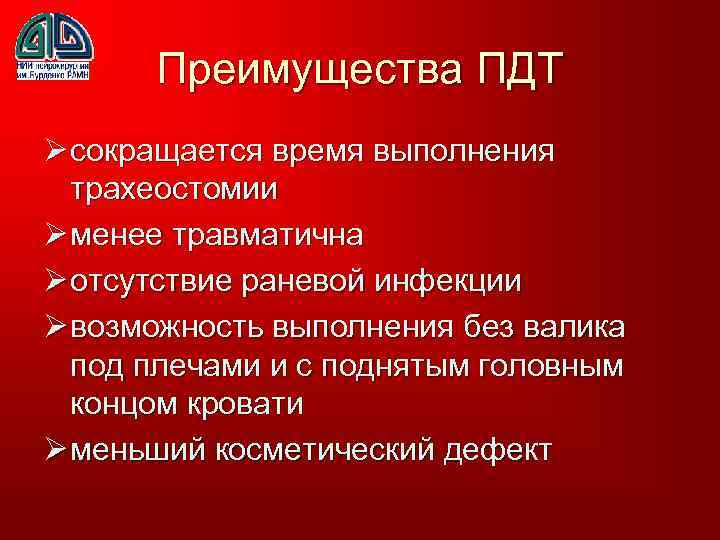

Преимущества ПДТ Ø сокращается время выполнения трахеостомии Ø менее травматична Ø отсутствие раневой инфекции Ø возможность выполнения без валика под плечами и с поднятым головным концом кровати Ø меньший косметический дефект

Преимущества ПДТ Ø сокращается время выполнения трахеостомии Ø менее травматична Ø отсутствие раневой инфекции Ø возможность выполнения без валика под плечами и с поднятым головным концом кровати Ø меньший косметический дефект

Преимущества ПДТ Ø сокращается время выполнения трахеостомии Ø менее травматична Ø отсутствие раневой инфекции Ø возможность выполнения без валика под плечами и с поднятым головным концом кровати Ø меньший косметический дефект

Преимущества ПДТ Ø сокращается время выполнения трахеостомии Ø менее травматична Ø отсутствие раневой инфекции Ø возможность выполнения без валика под плечами и с поднятым головным концом кровати Ø меньший косметический дефект